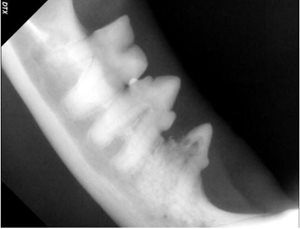

Another lovely feline friend, eight-year-old “Sir Ruby” had dentistry with us last month. During his annual health exam in May 2018, we observed that his teeth were moderately dirty, but by August 2018 there was significant suspicion of resorptive lesions noted by the veterinarian during a routine dental examination. The doctor noted the tell-tale red spot and significant gingivitis associated with his lower premolars. A dental procedure was recommended. During Sir Ruby’s dental surgery, gentle dental probing confirmed crown resorption and associated oral pain. X-rays of the affected teeth confirmed root resorption, as well. The teeth were extracted, Sir Ruby recovered quickly and is back to his normal happy self.

Left Lower Premolars